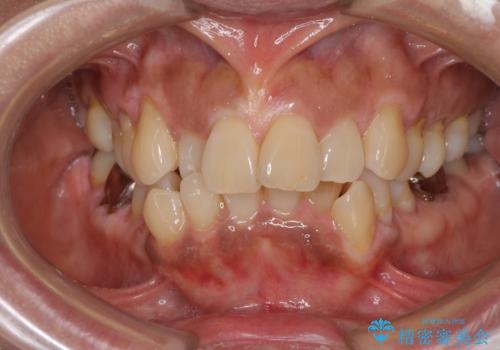

[ 再生治療・歯周外科・小矯正・セラミック補綴 ] 前歯の歯周病治療

担当医 大元洋佑

![[ 再生治療・歯周外科・小矯正・セラミック補綴 ] 前歯の歯周病治療の症例 治療前](https://seimitsushinbi.jp/wp/wp-content/uploads/2022/12/83065c2454a29ed71cf190e15a6106f4-500x350.jpg?v=1671673398)

![[ 再生治療・歯周外科・小矯正・セラミック補綴 ] 前歯の歯周病治療の症例 治療後](https://seimitsushinbi.jp/wp/wp-content/uploads/2022/12/ec16e37ee53325a6f6629b94759f5513-500x350.jpg?v=1671673454)